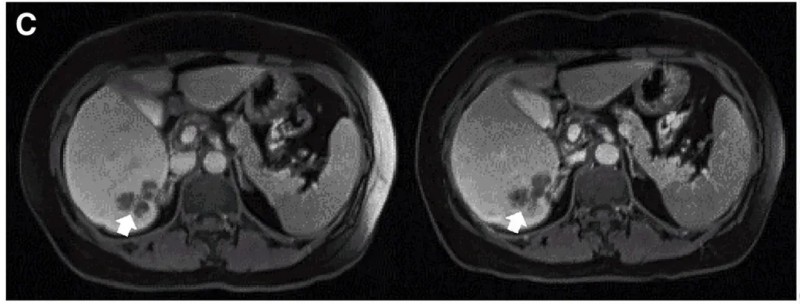

另一例P10患者接受DL4剂量治疗后,MRI检查证实其肝内一处病灶缩小(详见下图C)。

▲图源“Molecular Therapy”,版权归原作者所有,如无意中侵犯了知识产权,请联系我们删除